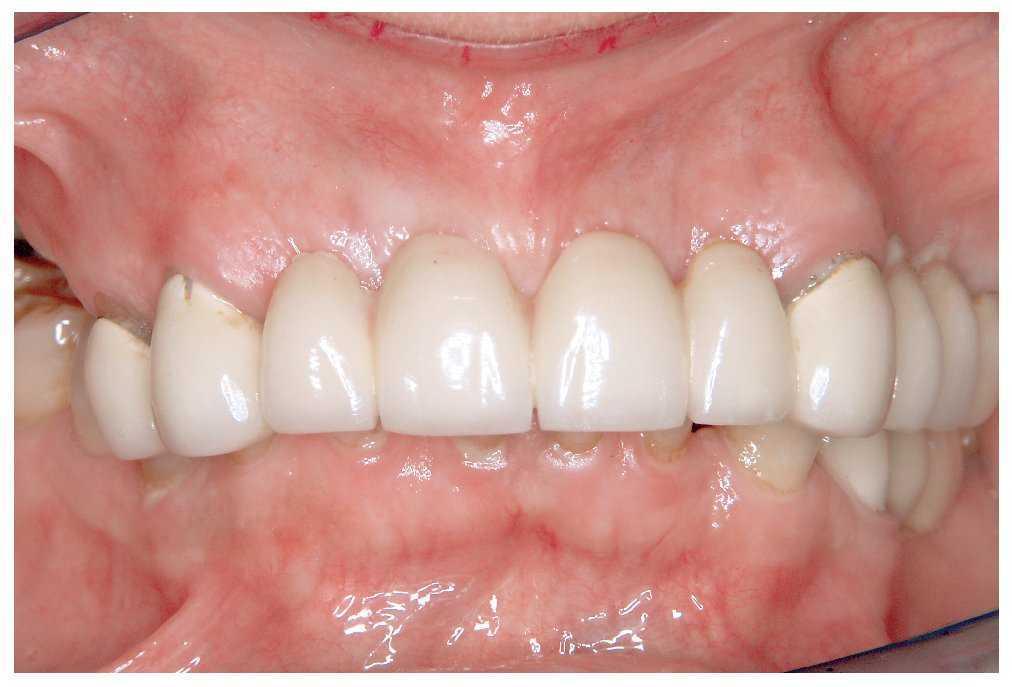

Si la rehabilitación protésica tiene por objetivo el aumento de la dimensión vertical para solventar una pérdida de la misma se debe llevar a cabo un análisis funcional clínico exhaustivo (fig. 5). En este contexto es irrelevante si el paciente ya lleva una prótesis que debe ser sustituida o si se deben restaurar dientes naturales dañados.

Figura 5. Situación inicial previa a un aumento de mordida.